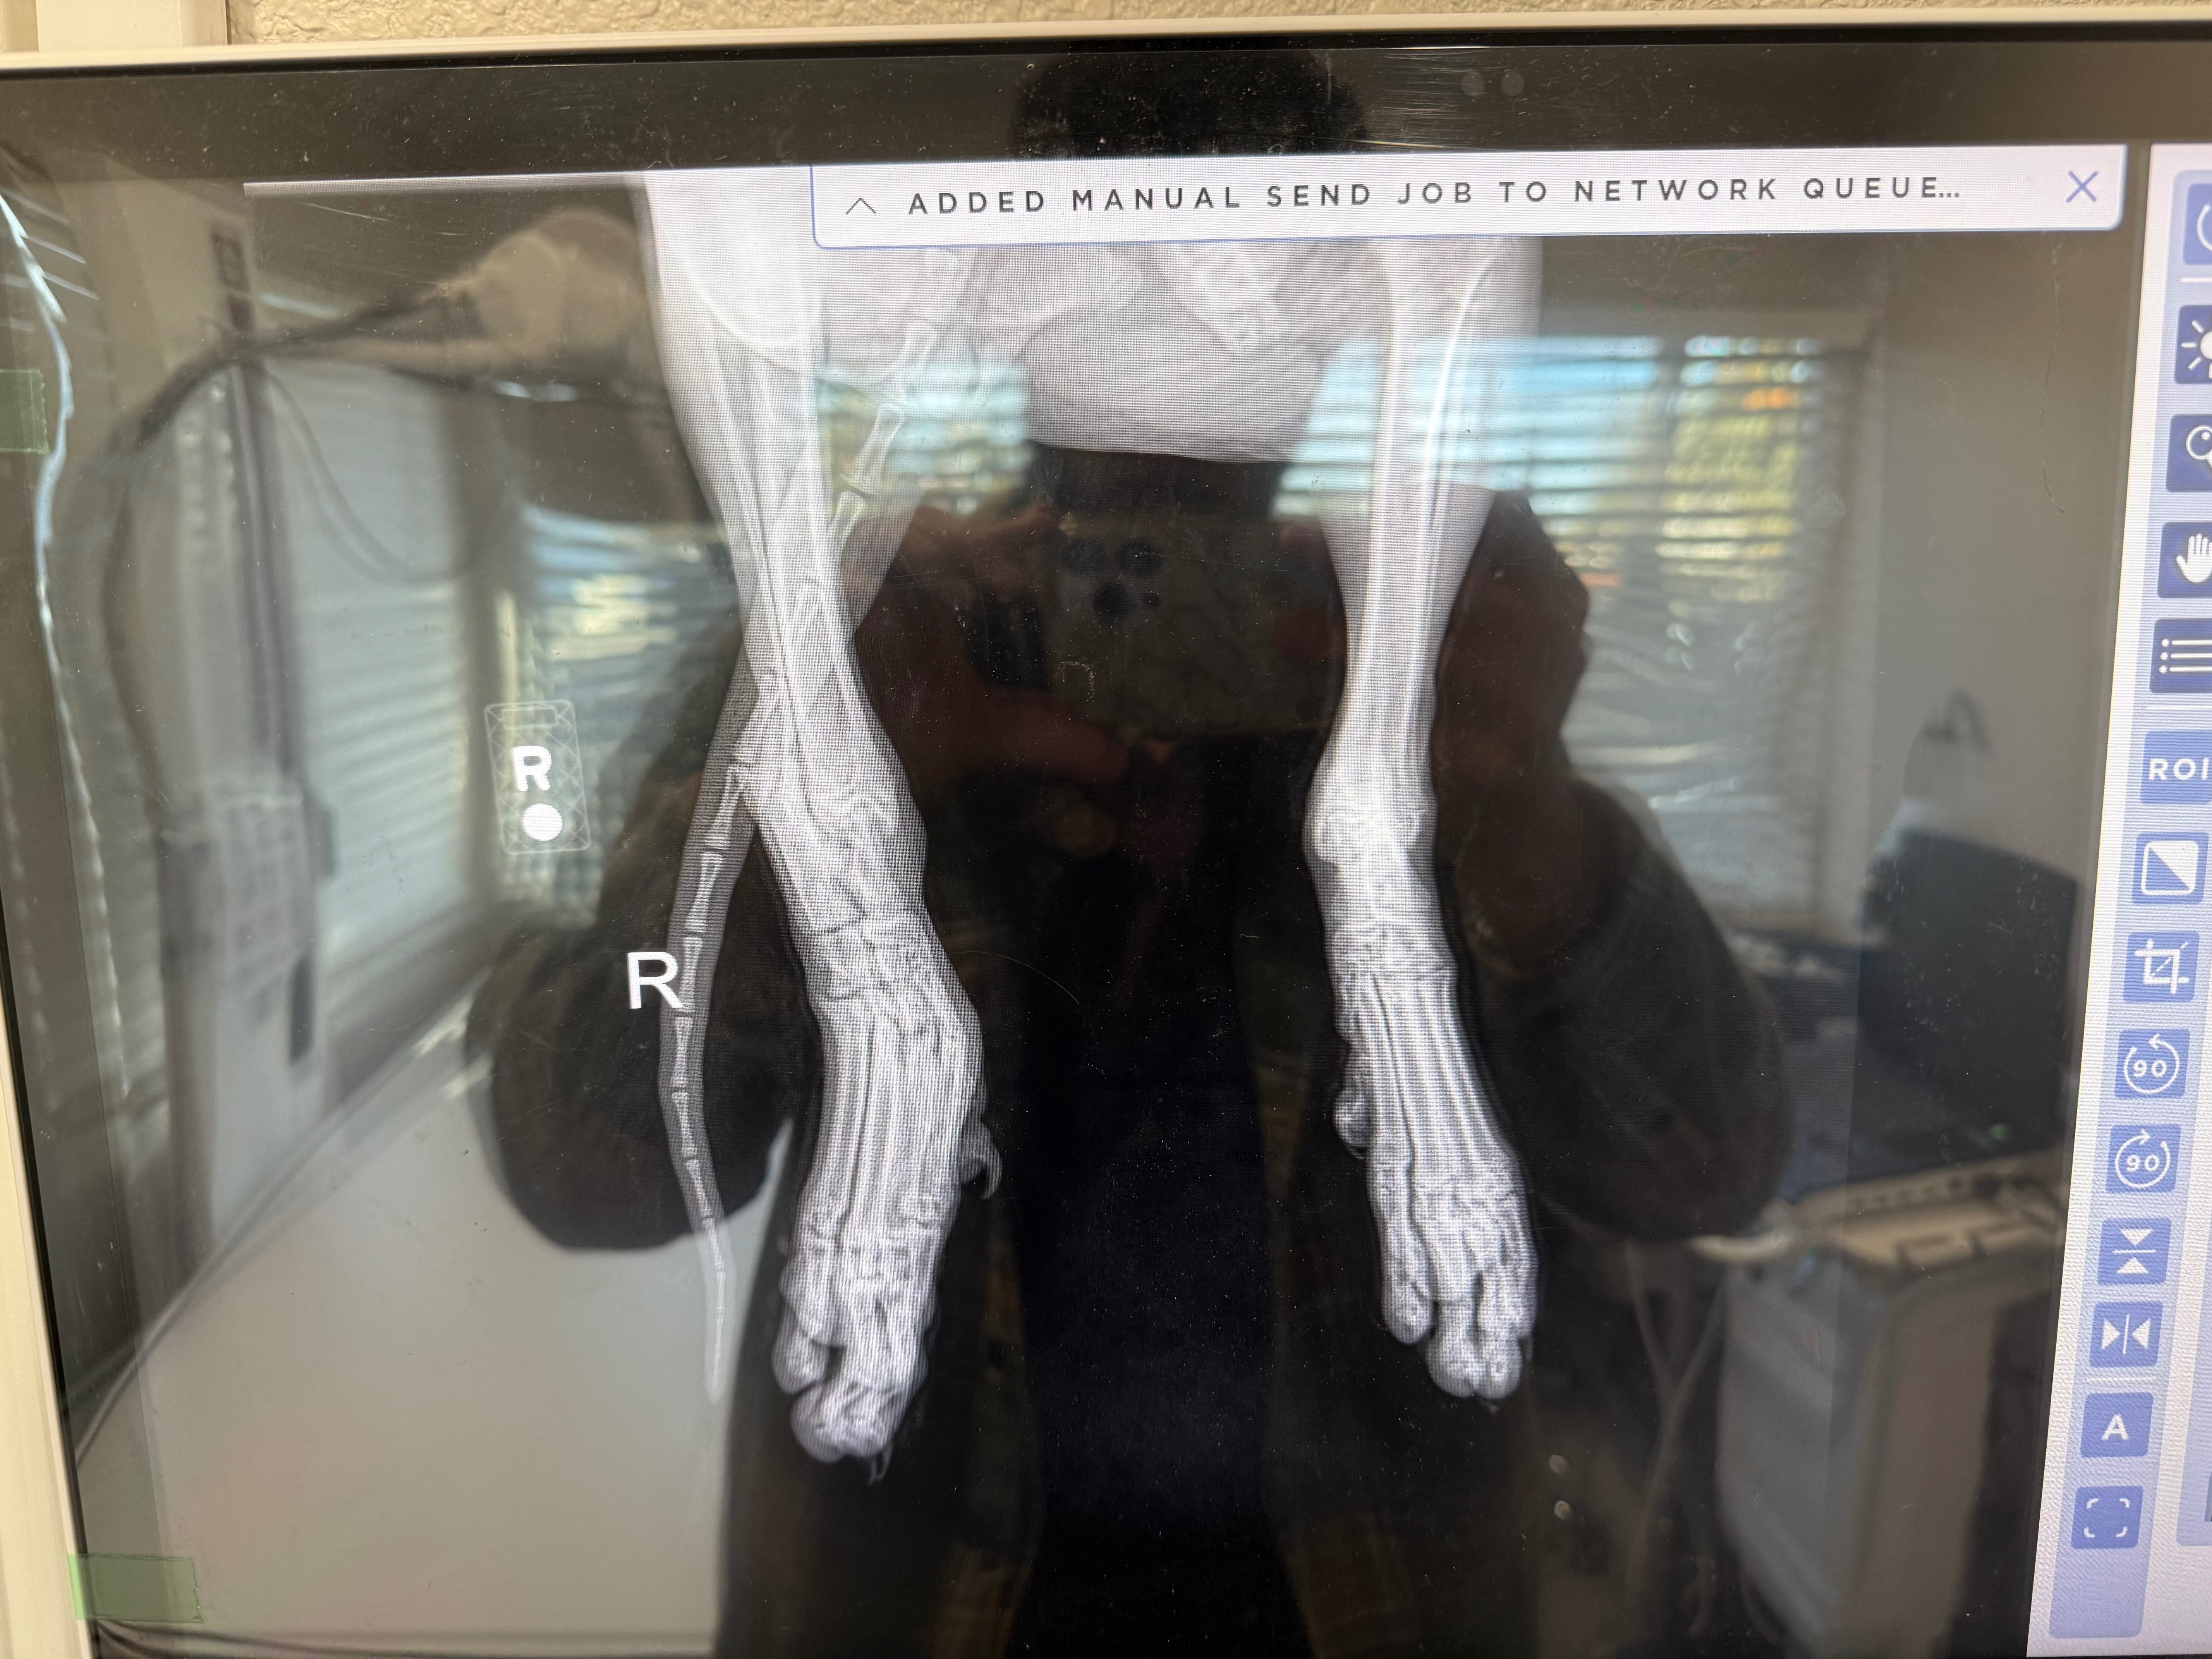

This sweet girl isn’t suffering from just one injury- she has multiple devastating breaks:

• Two broken hips

• Multiple fractured toes

• An ankle snapped in half and healing improperly

The veterinary team believes she has likely been living with these injuries for months. Dumped. Alone. Then likely struck by a car and somehow still surviving through unimaginable pain.